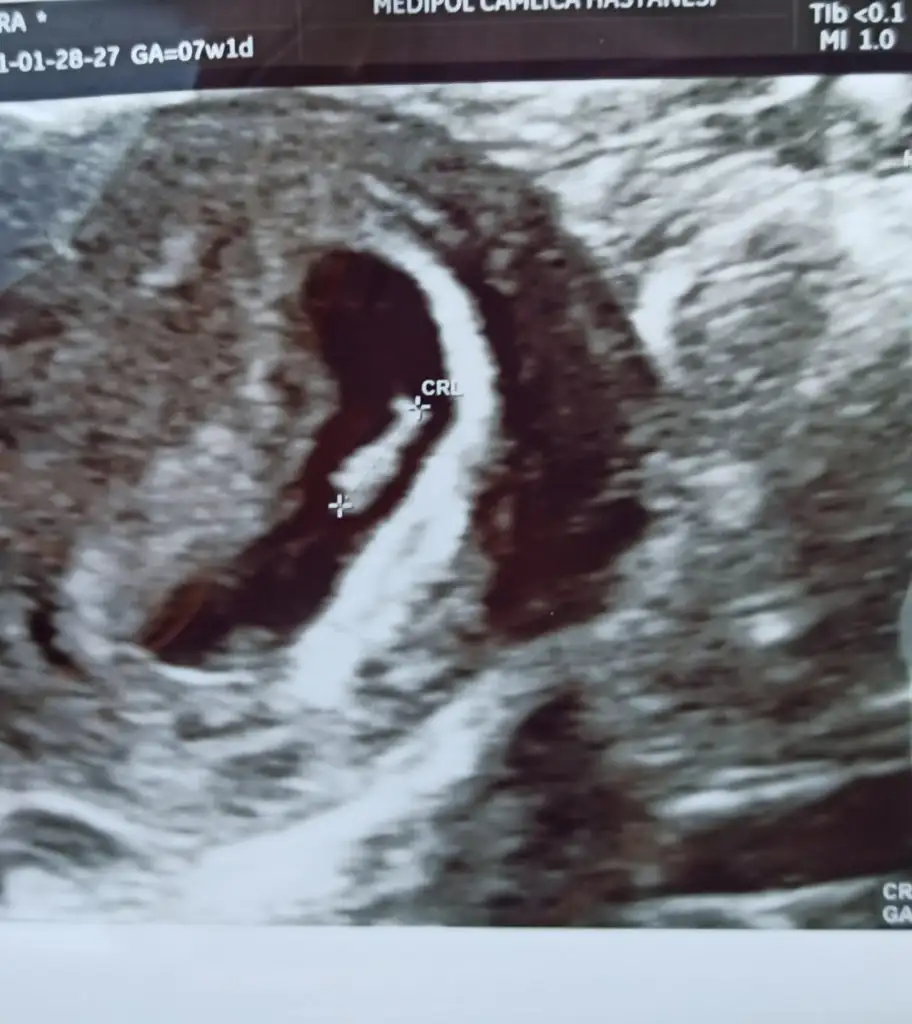

Ben hic anlamıyorum canim yaa. Ama kesenin seklinden kiz mi acaba dedimBide anlayan arkadaslard rica etsem cinsiyet tahmini yapabilir mi nütfeen nütfeen

Maşallah.saglikla gelsinBenimkine de bakın bari anlayan arkadaşlar

Ben hic anlamiyorum canim ya. Guya kese fasulye seklindeyse erkek oluyormus. Ama sende bebek sagda ve plasenta da sagda. Kiz diyorlar boyle olunca daİnşallah hepimizincinsiyetten anlıyor musun gerçi hiç önemli değil de insan merak ediyor yine de

Evet fasulye olayını ben de duydum. Bakalım sağlıkla gelsin inşallah illa ki biri olacakBen hic anlamiyorum canim ya. Guya kese fasulye seklindeyse erkek oluyormus. Ama sende bebek sagda ve plasenta da sagda. Kiz diyorlar boyle olunca davelhasili ne desem bilemedim

Geçen hafta bizde görmedik ve duymadık canım 8+5 gözüküyo şuan hemen hemen aynı zamanda gitmişiz benim kese 10 mm di. Korkuyorum bende boş gebelik diye. Tüp bebek dr um erken dönemde olabiliyor dedi önümüzdeki hafta çok önemli dedi bende bekliyorum. Stres yapma sende eğer sağlıklı iseler bebişlerimiz bizimle olurKarından da vajinal de duyamadık kalp atışını7+1 kese 24 mm olmuş,ama kalp atışı yok.Haftaya perşembeye randevu verdi,sanırım önce bakacak kalp atışı yoksa kürtaj yapacak